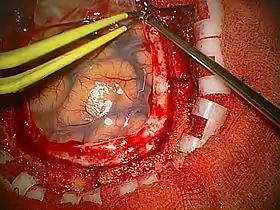

Diagram of the elements of a craniotomy.

Human craniotomy is usually performed under general anesthesia but can be also done with the patient awake using a local anaesthetic; the procedure, typically, does not involve significant discomfort for the patient. In general, a craniotomy will be preceded by an MRI scan which provides an image of the brain that the surgeon uses to plan the precise location for bone removal and the appropriate angle of access to the relevant brain areas. The amount of skull that needs to be removed depends on the type of surgery being performed. The bone flap is mostly removed with the help of a cranial drill and a craniotome, then replaced using titanium plates and screws or another form of fixation (wire, suture, etc.) after completion of the surgical procedure. In the event the host bone does not accept its replacement an artificial piece of skull, often made of PEEK, is substituted. (The PEEK appliance is routinely modeled by a CNC machine capable of accepting a high resolution MRI computer file in order to provide a very close fit, in an effort to minimize fitment issues, and therefore minimizing the duration of the cranial surgery.)